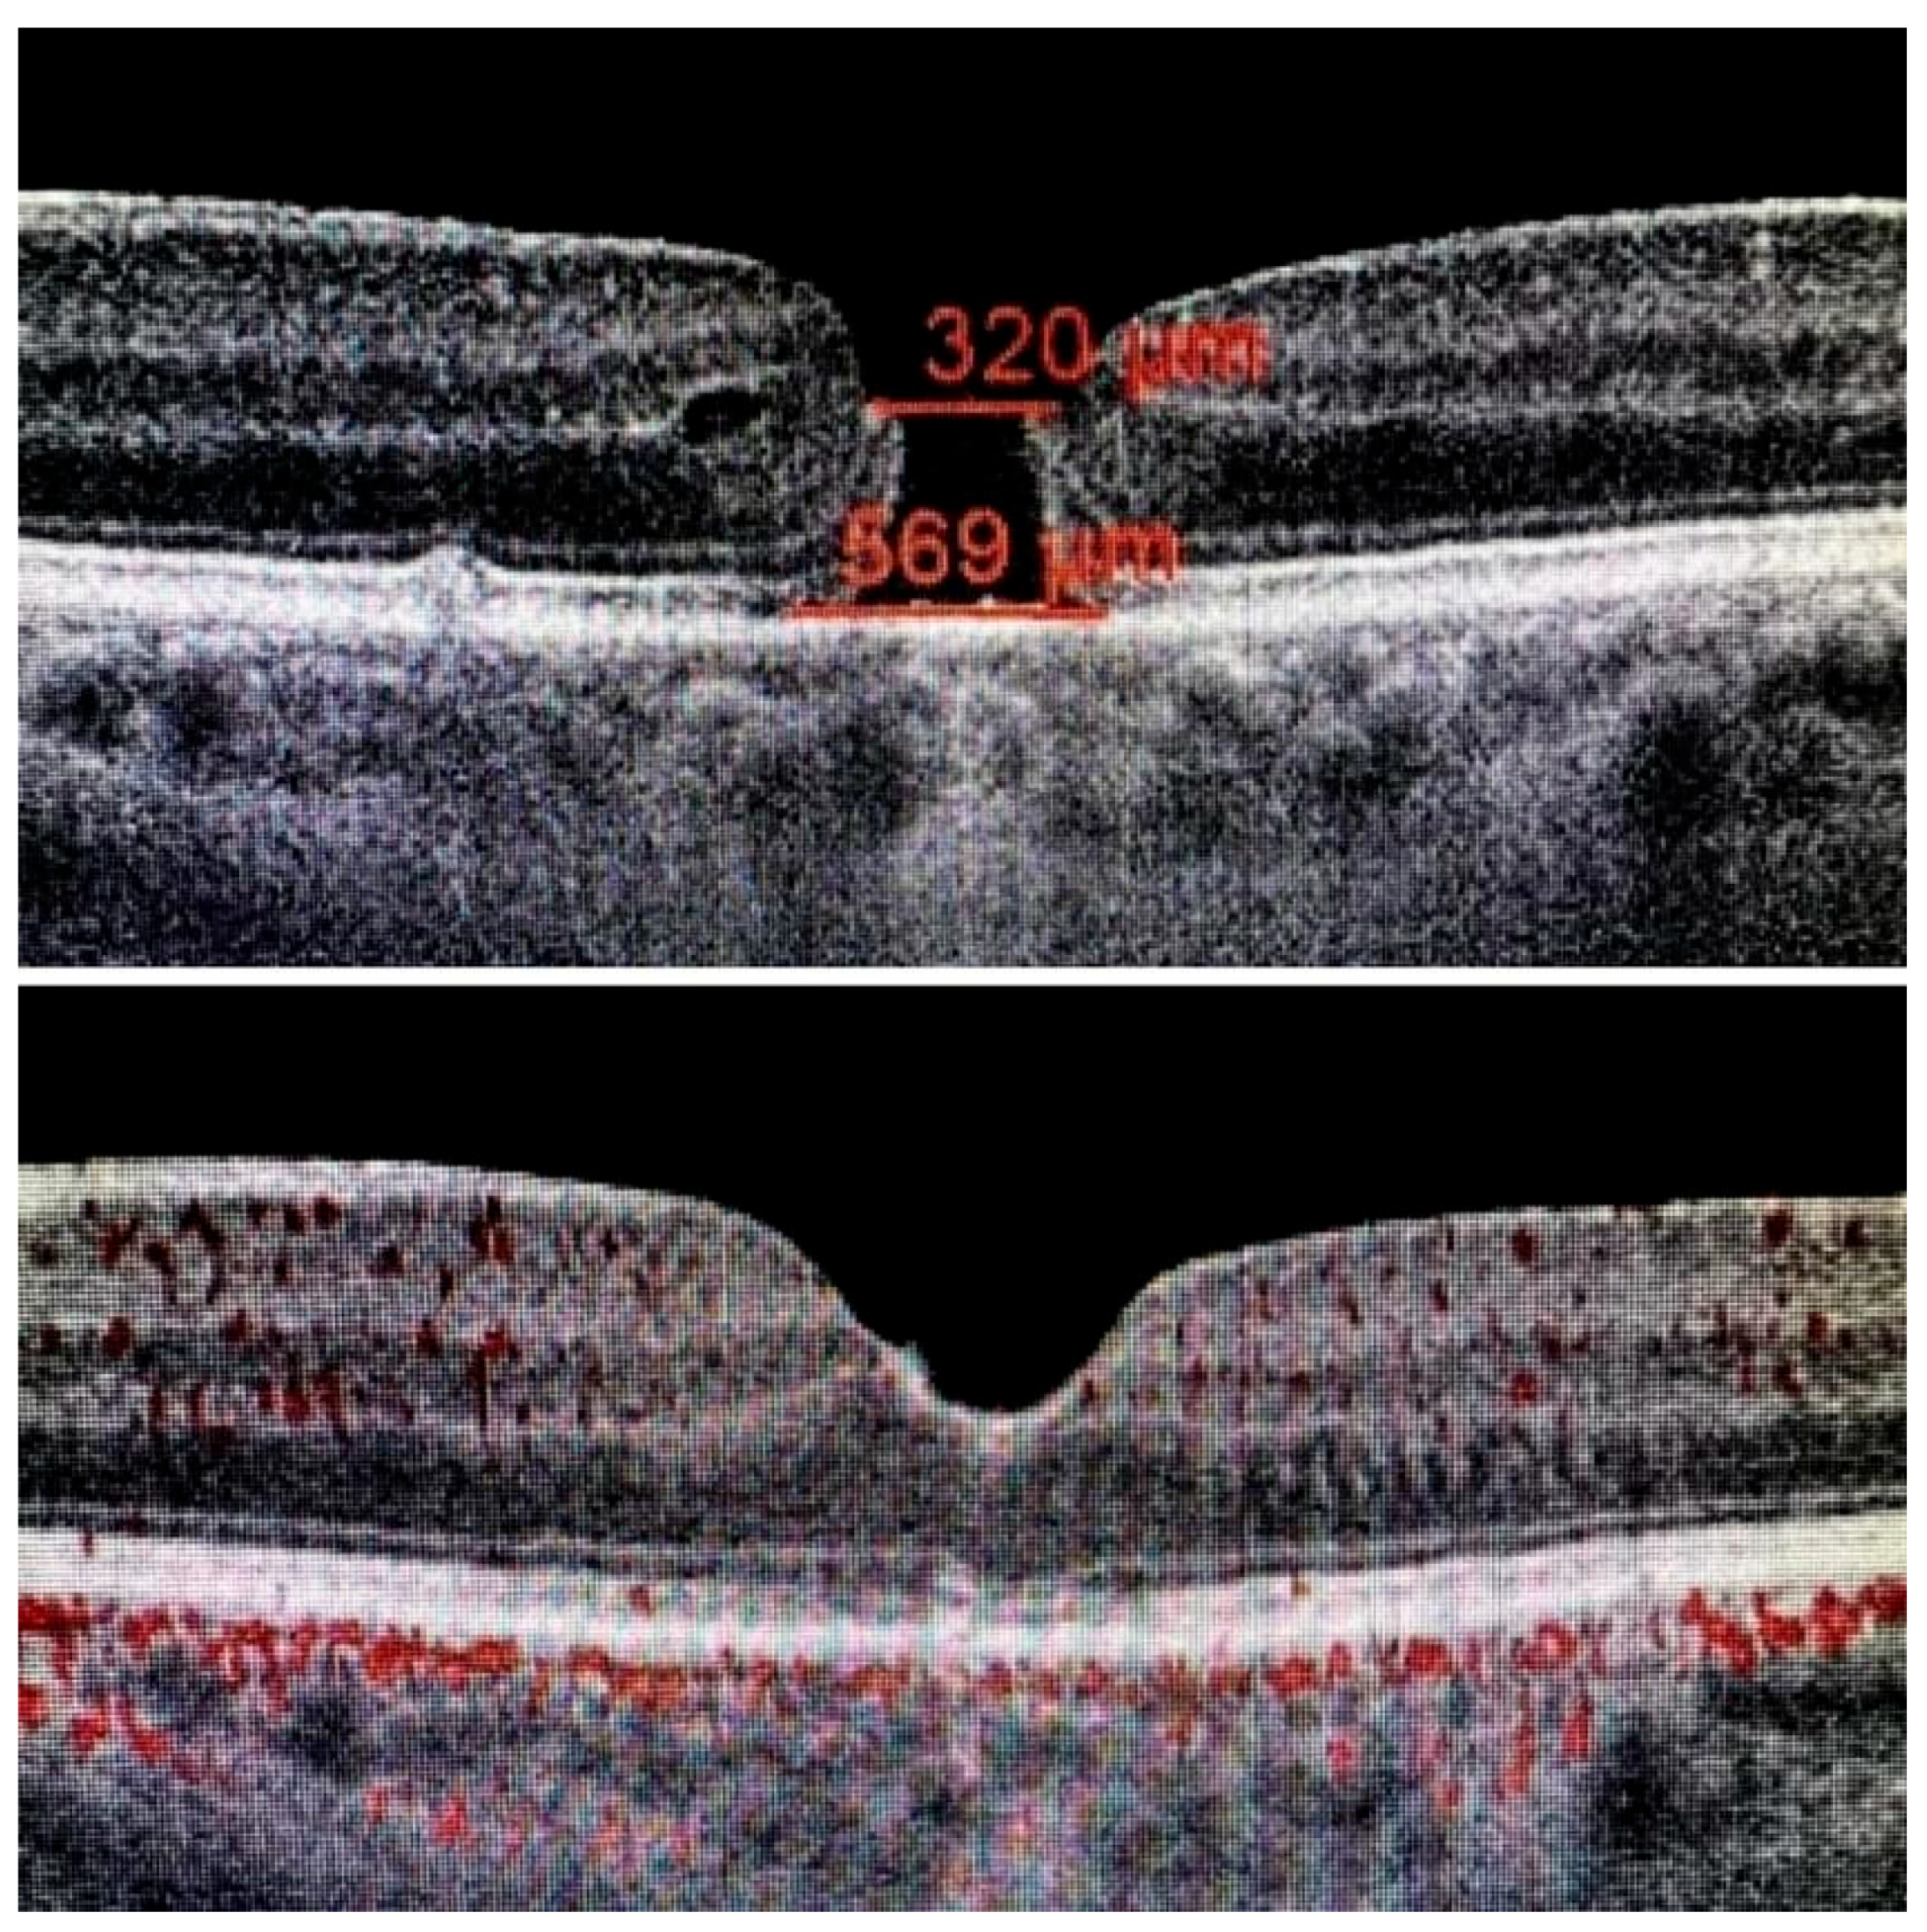

The ILM was peeled without the use of vital dyes, employing visualization techniques for transparent structures. A 25G silicone soft-tip cannula was used to gently approximate the edges of the macular hole under a balanced salt solution. Triamcinolone aceonide (Kenalog) was deposited on the ILM surface to enhance its visibility, and additional guidance was provided by instrument shadows under green-light illumination. Peeling was initiated at the point of weakest adhesion between the ILM and the retina. A pair of vitreoretinal forceps (e.g., Alcon Grieshaber AG, Schaffhausen, Switzerland) was used to gently grasp and lift the ILM to initiate separation. The extent of peeling covered an area of approximately 2–3 optic disc diameters around the hole to relieve tangential traction. Following ILM peeling and centripetal tissue mobilization, the macular hole edges were approximated under balanced salt solution or, in selected cases, perfluorocarbon liquid. Closure was monitored in real time using high-resolution intraoperative OCT (RESCAN™ 700 integrated with OPMI LUMERA® 700 microscope, Carl Zeiss Meditec AG, Jena, Germany). Representative intraoperative OCT images before and after ACP application are presented in Figure 1, Figure 2 and Figure 3.

Figure 1. Intraoperative images before ILM peeling and after macular hole closure, with superficial approximation of the edges using a silicone-tipped cannula.

Figure 2. Top image: visible internal limiting membrane (ILM); bottom image: ILM removed—without ILM peeling, perfect macular hole closure is not achievable.